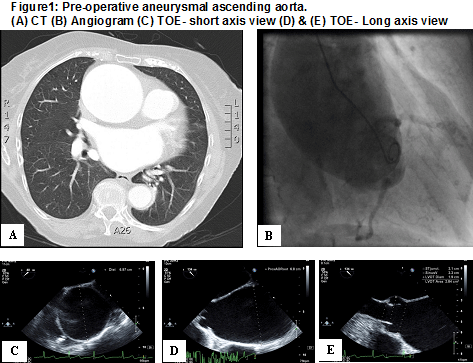

CT angiogram aorta (Figure 1A) reported the following measurements:

- Aortic annulus - 2.8 x 1.9 cm

- Sinus of valsalva maximum measurement - 3.5 cm

- Sino tubular junction - 3.5 cm

- Ascending aorta at the level of right pulmonary artery - 6.4 cm

- Ascending aorta just proximal to the brachiocephalic trunk measures 5.2 cm

- Aortic arch at the level of left subclavian artery measures 3.4 cm

- Descending thoracic aorta at the level of the hiatus measures 2.9 cm

- Abdominal aorta just inferior to the renal artery measures 2.2 cm

Her coronary angiogram (Figure 1B) excluded any significant flow limiting disease, but showed very markedly dilated ascending aorta.

Pre-cardiopulmonary bypass trans-esophageal echocardiogram showed dilated ascending aorta with the following measurements:

- TOE- short axis view: distal ascending aorta= 6.97 cm (Figure1C)

- TOE- Long axis view: proximal aortic root= 6.8 cm (Figure1D)

- TOE- Long axis view: STJ=3.1 cm; Sinus of valsalva= 3.3 cm; LVOT diameter = 1.9 cm (Figure1E)